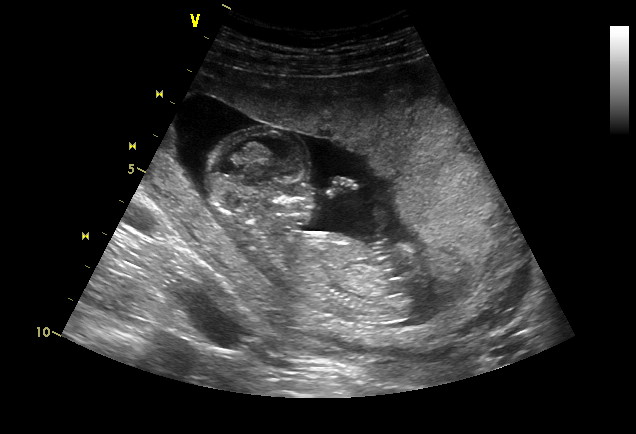

Ahoj :) Tak mi ta kontrola konečně vyšla.POprvé midoktor dělal UZ přes břišní stěnu a jsem 13+1.Termín mám dle měsíčků 25.12 a druhý dle UZ 31.12.Za dva týdny mám další kontrolu + odběry krve tak doufám že se konečně něco dozvim.Protože se po těch všech problemech bojim že něco nebude ok,tak doufam že bude maly v pořadku..Pan doktor mi maléhoi vyfotil,ale měl pro mě i špatné stránky.Dva dny zpět sem dost krvacela,kde mi na pohotovosti dli injekci Dicynonu na zástavu.Včera mi lékař na kontrole řekl že je tam další hematom a to větší než ten před týdnem tak mám docela strach.Prý když se krvácení zopakuje může dojítk odděení plodových obalů a kpotratu.Miminko se má k světu,taže už jen ležim a vstávám jen na záchod,protože o malého opravdu přijít nechceme.